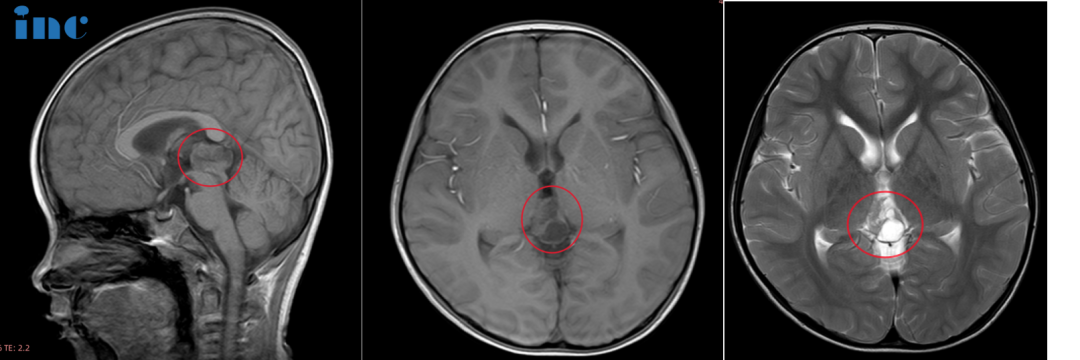

2021年,6岁的鑫鑫因意外摔破头皮就诊。CT检查发现松果体区阴影和钙化灶,MRI进一步确认病灶大小为22×14×17mm。回顾既往,父母才意识到孩子曾有身高发育缓慢、走路不稳易绊倒的表现。到2023年7月,最新MRI显示病灶已增大至25×19×15mm。此时的鑫鑫睡眠不稳定、逻辑理解能力下降、记忆力衰退,还出现了一系列心理问题。眼看孩子的成长之路可能因此受阻,鑫鑫的父母开始寻求更好的治疗方案。

为争取更高的生存率,鑫鑫的父母在INC国际神经外科医生集团协调下,寻求巴特朗菲教授进行手术切除。松果体区肿瘤的手术入路一般包括幕下小脑上入路、枕下小脑幕入路、后纵裂经胼胝体入路等,最适合的方式主要取决于肿瘤的解剖学特点。针对鑫鑫的情况,巴特朗菲教授采取幕下小脑上入路,最终实现了肿瘤的全切除,并尽力减少了对周围组织的损伤,这对预防后期肿瘤复发起到了关键作用。